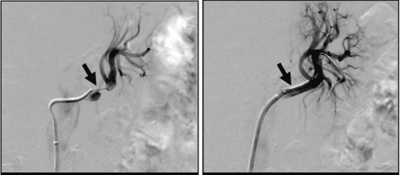

Nierenarterie

zentrum-fuer-mikrotherapie-nierenarterie

Engstelle der linken Nierenarterie (Pfeil links), welche ebenfalls mit einer Gefässstütze erfolgreich erweitert werden konnte (Pfeil rechts).

© Interventionelle Radiologie - Swiss Intervention